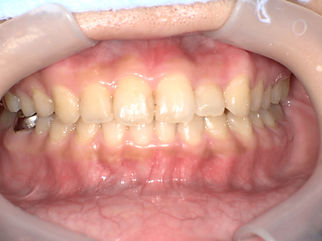

症例1 中等度~重度の叢生 インビザライン治療 品川区五反田在住30代女性

【治療前】

30代女性の症例です。

上下の前歯の数本の歯にねじれがある、上前歯のでっぱり感が気になるとのことでした。

また、下の前歯の前後の凸凹が気になるとのことです。

出っ歯に見られる前歯にコンプレックスを感じてらっしゃったとの ことで、見えない矯正のインビザライン矯正で治療しました。